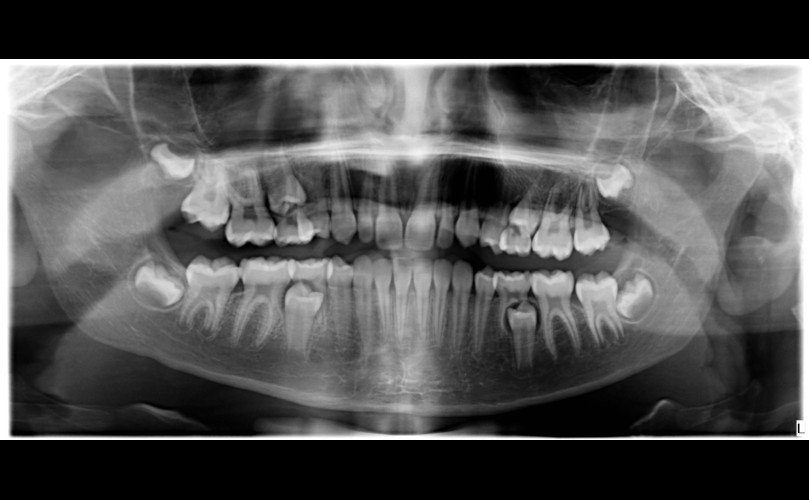

La importancia del perfil en el tratamiento de ortodoncia

Dentro de poco os enseñaremos las fotografías de este caso. Por ahora os dejamos con la radiografía lateral previa al tratamiento y la...